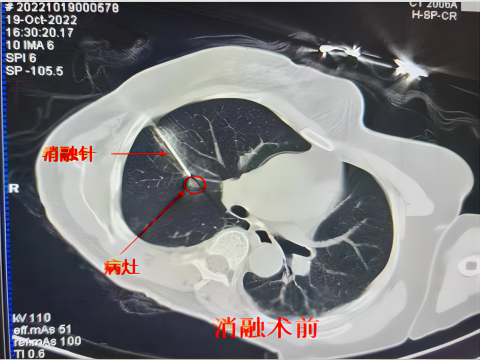

通过将一根1.7-3毫米的中空钢针,穿刺进入肿瘤,先注入氩气,迅速降温至-160摄氏度,冰冻肿瘤数分钟,再注入氦气,快速升温至20-30摄氏度,让肿瘤细胞在短时间内经历“冰火两重天”而破裂损毁。或许这听起来有点匪夷所思!这就是氩氦刀冷冻消融技术。

氦氩刀是什么【航医说医】“冻死”肿瘤--氩氦刀冷冻消融技术,肿瘤治疗新选择_https://www.jmylbn.com_新闻资讯_第12张微创治疗。在局部麻醉下,通过超声、CT等仪器引导或者直视下操作,使用粗细如牙签的冷冻探针穿刺至肿瘤组织,因手术范围仅局限于病灶,所以临近正常组织损伤较小,手术并发症少、创伤小、痛苦小、恢复快。